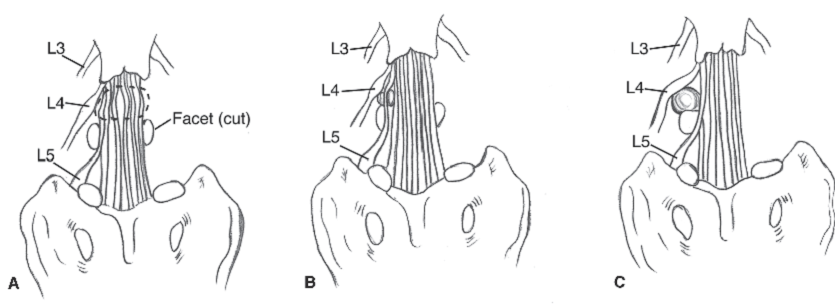

Rothman và Marvel đã chia thoát vị đĩa đệm ra sau thành 3 loại:

- Loại thoát vị trung tâm (central) chủ yếu chèn ép tủy sống gây bệnh lý tủy.

- Loại thoát vị cạnh trung tâm (sau-bên, posterial-lateral) chèn ép cả tủy và rễ thần kinh gây ra bệnh lý tủy rễ.

- Loại thoát vị cạnh bên (xa bên, far-lateral) còn gọi là thoát vị lỗ ghép chủ yếu chèn ép rễ thần kinh gây ra bệnh lý rễ.

HÌnh 3: Phân loại thoát vị đĩa đệm theo liên quan với rễ thần kinh và ống sống. (A) thoát vị trung tâm, (B) thoát vị cạnh trung tâm, và (C) thoát vị xa bên

Cách phân loại này có ý nghĩa rất lớn trong lâm sàng.